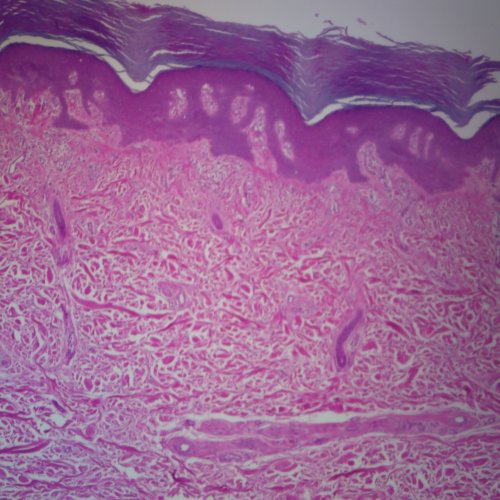

• Product Name: Human Plantar Skin Slide, 7 m, H&E

Explore the thick layer of integumentary tissue taken from the bottom of the human foot. Using this slide students can easily identify different layers of the skin. The top layer of the epidermis the stratum corneum is thick and keratinized. The cells of this layer function as protection and are constantly shed. Stained with hematoxylin and eosin.